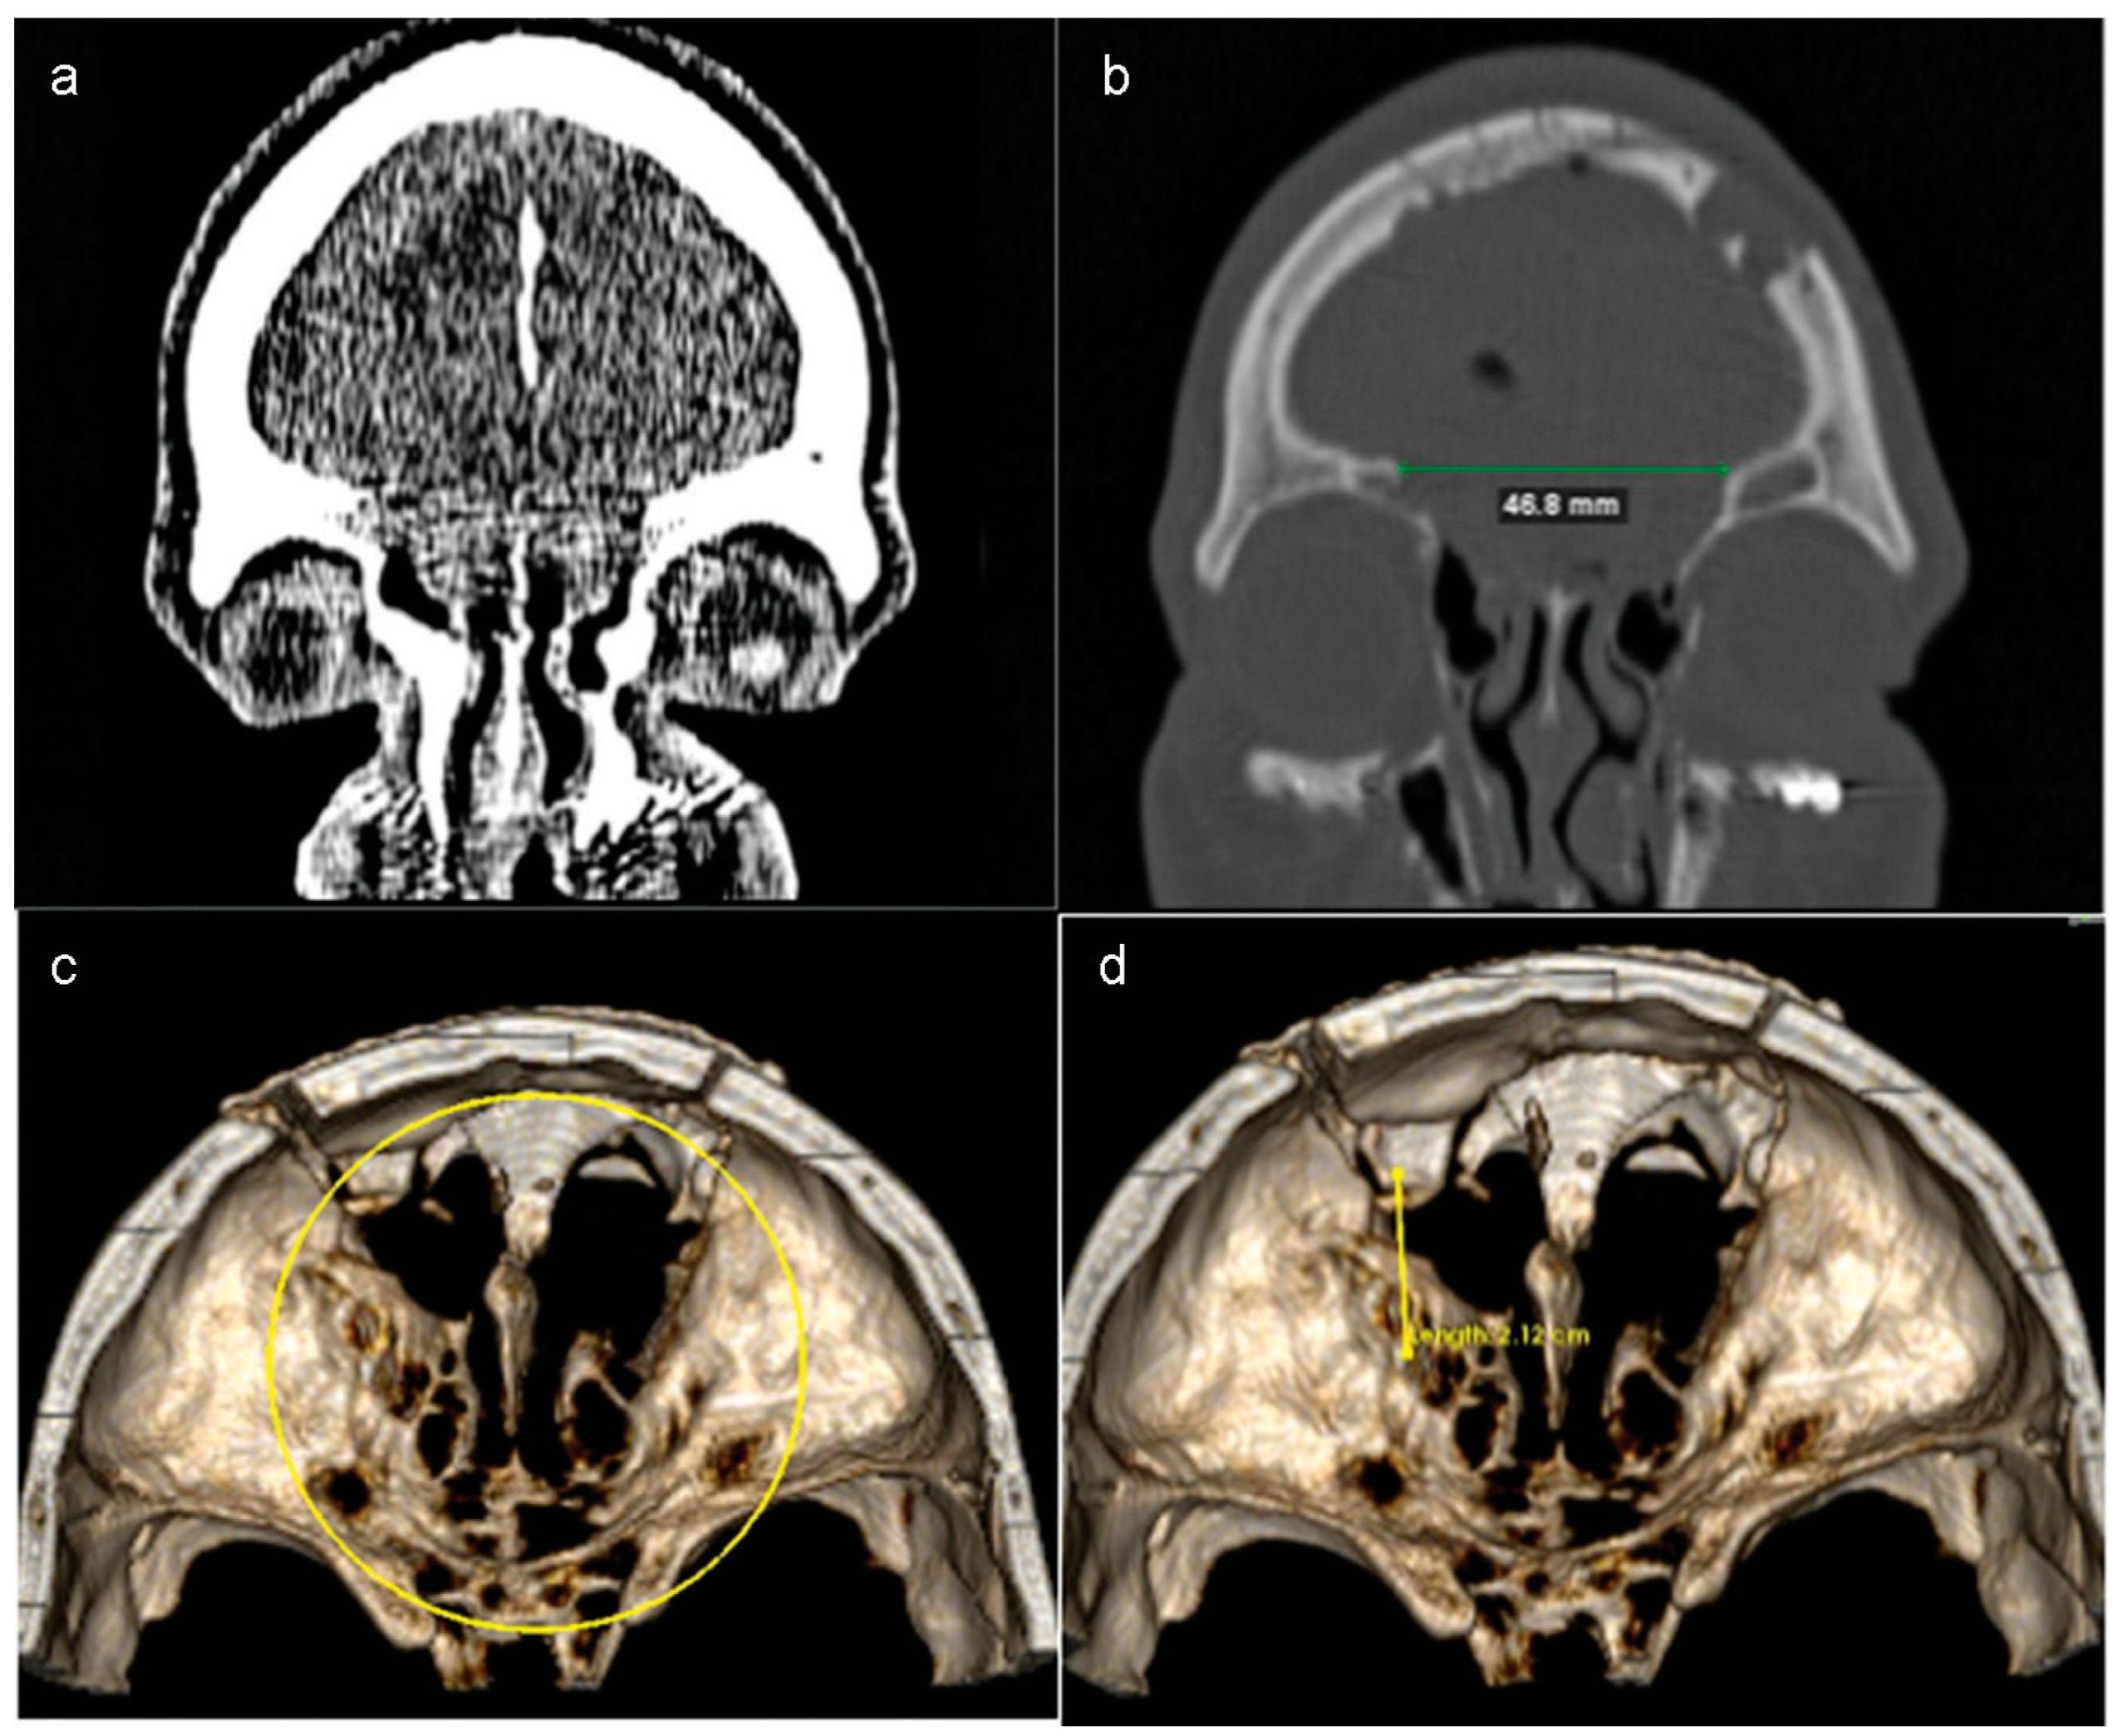

After 18 days, the same patient returned with pulsatile headache, dizziness, and nausea. Besides this clinical sign, a new CT scan revealed a large encephalocele associated with an extensive defect of the anterior skull base (Figure 5a–d).

Before the second procedure, the dimensions of bone defect were measured using 3D computer software and the titanium mesh contoured for a more accurate implant (Figure 6b). Thus, the operation was planned as shown in Figure 7. The planned reconstruction started with the same steps of the first procedure. Then, the contoured mesh was placed over the anterior skull base defect with the help of 4-mm screws (Figure 8a,b).

Figure 5. (a and b) Eighteen days after the procedure, the patient returned and a new CT scan revealed a large encephalocele. The protrusion of the brain through the nasal cavity was associated with an extensive defect of the anterior skull base. (c and d) Three-dimensional volume rendering images showed that the osseous defect had increased after first surgery.